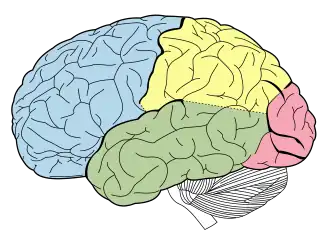

Principal fissures and lobes of the cerebrum viewed laterally. (Parietal lobe is shown in yellow) | |